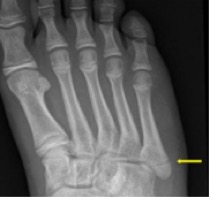

Een breuk van het 5e middenvoetsbeentje komt vaak voor. De middenvoetbeentjes zijn de botten in het midden van uw voet. Het 5e middenvoetbeentje zit aan de kant van uw kleine teen. U krijgt bij behandeling een soort kous en een stevige brace. De kous heet een tubigrip, de stevige brace heet een walker.

| U heeft een breuk in het middenvoetsbeentje van uw kleine teen.U herstelt meestal goed.Een afspraak op de polikliniek is meestal niet nodig.U draagt de eerste 4 weken een walker. Vanaf de eerste dag kunt u op uw voet staan. Doe dit steeds iets langer. Stop als uw voet te veel pijn doet.Als u de walker niet meer draagt, begint u met oefeningen. Oefeningen zijn belangrijk om te zorgen dat uw voet niet stijf wordt. De oefeningen staan hieronder. Heeft u tijdens het herstel vragen of klachten? Neem dan contact op met het ziekenhuis waar u onder behandeling bent. |

De breuk komt vaak voor en herstelt meestal goed. U krijgt een tubigrip. Dat is een soort kous. Ook krijgt u een walker. Dat is een stevige brace. Zo heeft u minder pijn en geneest de breuk het snelst.